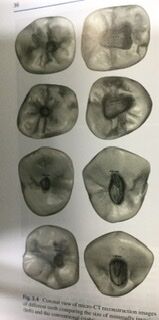

歯の根っこの辺りを半分にして、顕微鏡で見た絵です。

そうすると歯頸部、歯の頭と根っこの境目、ウエスト部分をたくさん削る事になり、歯が薄くなって破れやすくなってしまいます。

超弾性を持つニッケルチタン製のファイル がある現代では、過剰に歯を削るべきではありません。